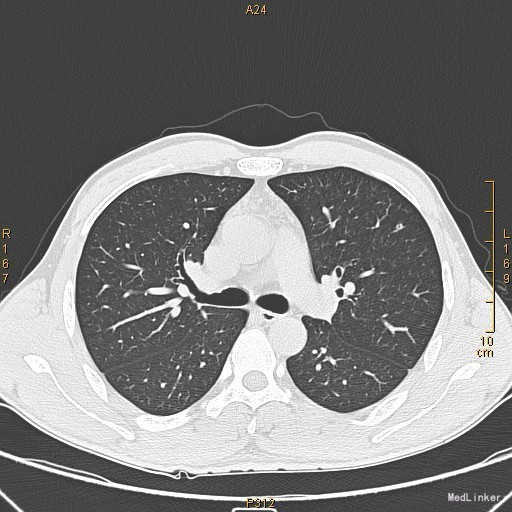

主诉:左眼睑下垂1年,加重半年。病史:患者1年前无明显诱因出现左眼睑下垂,抬起困难,伴视物重影,无言语不能、吞咽困难,无发热、头痛、恶心、呕吐、头晕、视物旋转、肢体麻木、饮水呛咳、视物模糊、肢体不自主运动、肢体抽搐、意识障碍、大小便失禁,休息后缓解,未予重视,半年来上述症状反复加重,10余天前至当地医院就诊,查新斯的明试验阳性,遂至我院神经内科就诊,胸部CT示:1、右肺尖钙化结节;2、胸腺增生。为了进一步治疗门诊拟“重症肌无力”收住我科。患者自起病以来,无发热、咳嗽、尿频、尿急、腹泻,无心悸、胸闷等,精神、食欲、睡眠好,体重无明显变化。

查体:左侧眼睑下垂,右侧眼裂宽10mm,左侧眼裂宽5mm。肺部查体未见异常。 辅查:新斯的明试验阳性。胸部CT示1、右肺尖钙化结节;2、胸腺增生。

该患者诊断“1.重症肌无力,眼肌型;2.右上肺钙化结节”明确,重症肌无力合并胸腺增生或胸腺瘤,有手术指征,我们为患者行胸腔镜下胸腺扩大切除术+右肺上叶楔形切除术。术后病理示:右上肺结节呈干酪样坏死,考虑结核。胸腺及纵隔脂肪均见淋巴增生。术后效果明显,患者左侧眼睑下垂较前好转,右侧眼裂宽10mm,左侧眼裂宽8mm,视物重影症状消失。